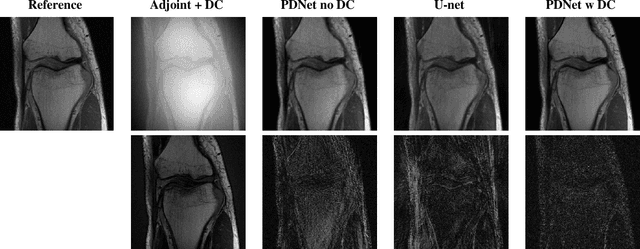

Abstract:Deep neural networks have recently been thoroughly investigated as a powerful tool for MRI reconstruction. There is a lack of research, however, regarding their use for a specific setting of MRI, namely non-Cartesian acquisitions. In this work, we introduce a novel kind of deep neural networks to tackle this problem, namely density compensated unrolled neural networks, which rely on Density Compensation to correct the uneven weighting of the k-space. We assess their efficiency on the publicly available fastMRI dataset, and perform a small ablation study. Our results show that the density-compensated unrolled neural networks outperform the different baselines, and that all parts of the design are needed. We also open source our code, in particular a Non-Uniform Fast Fourier transform for TensorFlow.